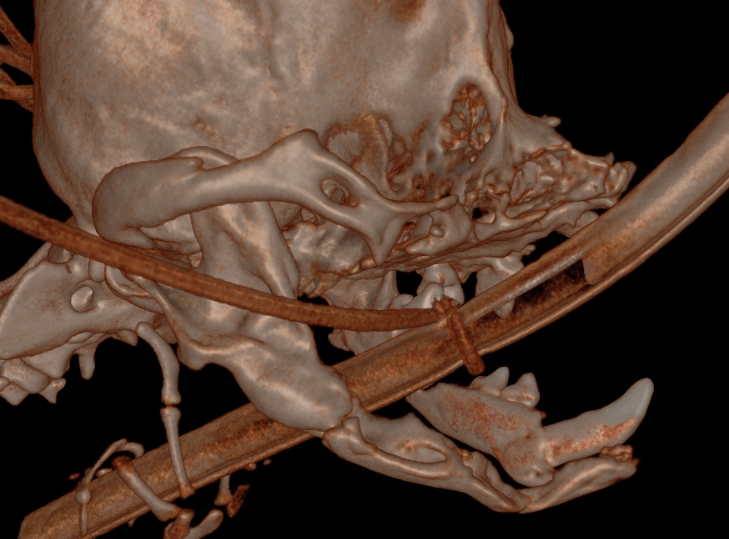

Coley Kay is severely brachycephalic and already had an almost ‘flat face.’ The fractures were present at the mid to caudal mandible at each lower first molar.

Above: CT slice with insufficient bone to be able to repair

Bilateral mandibulectomy through the fracture sites along with removal of the diseased teeth. Coley Kay presented with only 7 of the 42 teeth remaining. Four of those 7 teeth were the structural, important teeth, yet all 7 were diseased beyond repair. The upper canine had a communication between the nose and the mouth (oral nasal fistula). All teeth remaining were removed and the small thin mandible portions were removed from the fracture sites forward. A cosmetic closure while rebuilding the lip vestibule to aid in retaining saliva was performed. The tongue will hang out, but it had done so often prior to the fall.